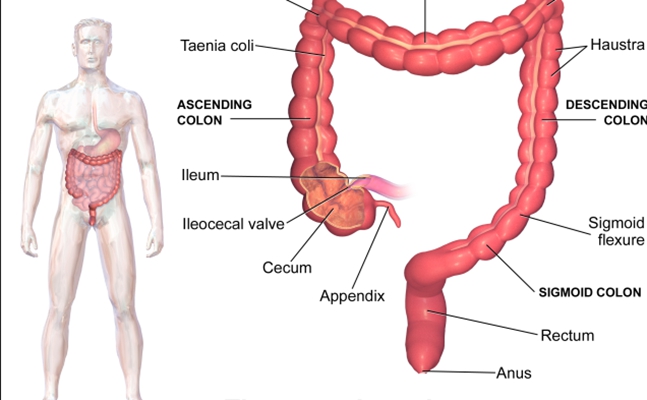

盲腸炎圖片

盲腸的位置 (50)

盲腸的位置 (6)

盲腸的位置 (7)

盲腸的位置 (8)

盲腸的位置 (9)

盲腸的位置 (46)

盲腸的位置 (47)

盲腸的位置 (48)

盲腸的位置 (49)

盲腸的位置 (5)